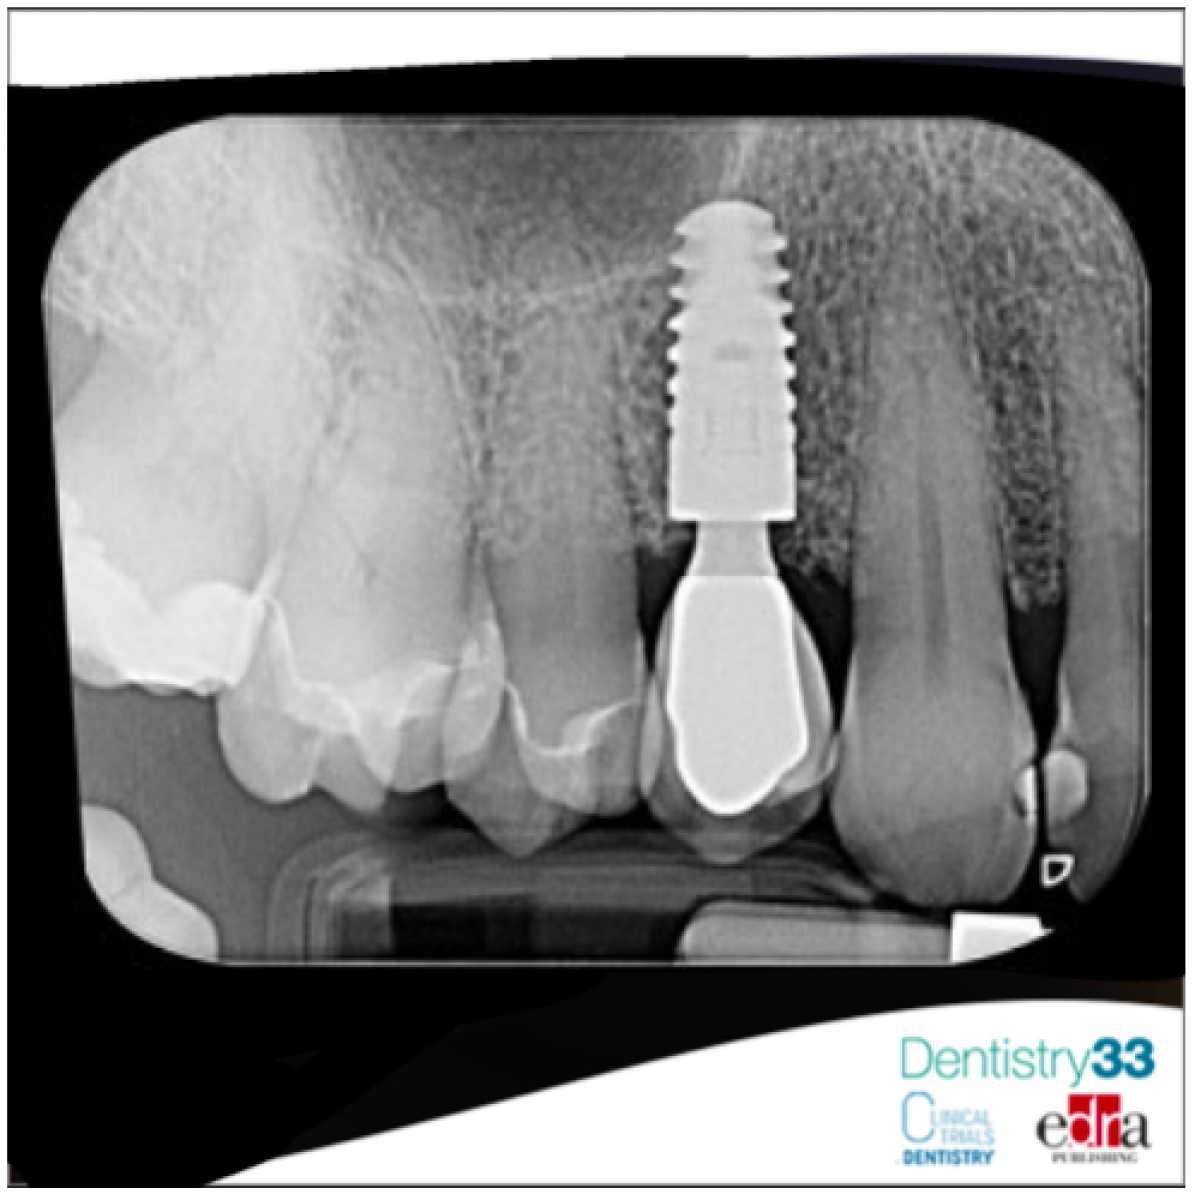

In a clinical study, published on Implant Dentistry, October 2019, the authors performed a functional and aesthetic evaluation of implant-prosthetic treatments in patients undergoing immunosuppressive treatment after organ transplants. The study involved a group of 21 patients on immunosuppressant therapy after transplant procedures. A total of 24 implants were placed in this experimental group. The control group included 15 subjects with 15 implants placed. The research protocol involved replacing a single missing tooth with a titanium implant. After 4 months, prosthetic rehabilitation with single crowns was carried out. After 24 months the preliminary treatment evaluation was performed. The main parameter calculated was the crestal bone level (CBL). A mechanical evaluation and objective measurement of the implant stability was also performed.

The median measurement of CBL crestal bone level in the experimental and control groups was found to be 0.325 mm (min 0 - max 0.95) and 0.5 mm (min 0.15 - max 1.8), respectively. Comparison of the CBL medians revealed a lack of significant differences between the experimental and control groups (P ¼ 0.089).